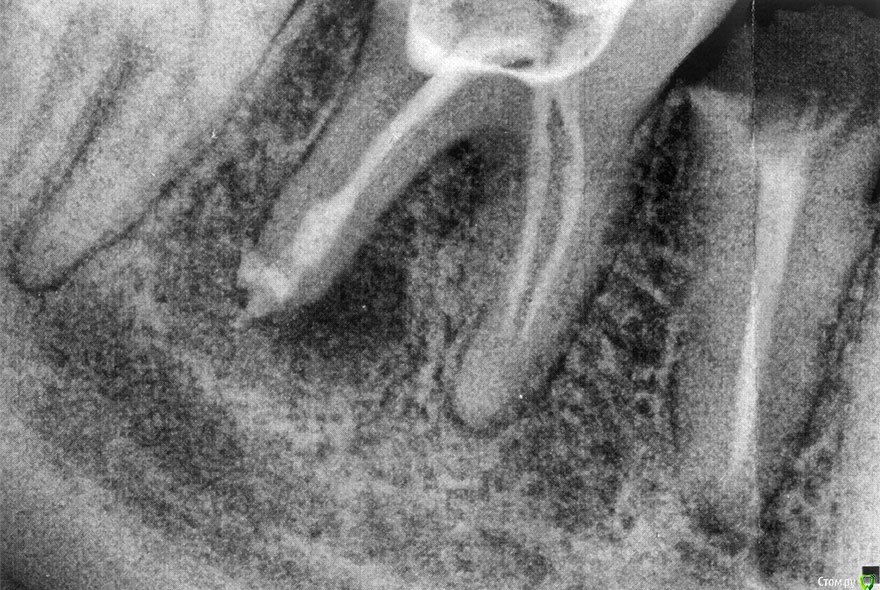

ximael Опубликовано 9 апреля, 2016 Поделиться Опубликовано 9 апреля, 2016 День добрый 46 зуб был запломбирован несколько лет назад.12 марта(суббота) появилась боль при надкусывании 46 зуба.13 марта зуб уже начал болеть просто так, не то, чтобы оч сильно.14 марта пошел в городскую поликлинику, сделали рентген, сначала хотели удалять, потом решили раскрыть. Сверлили, но, как позже оказалось, так и не досверлили.17 марта пошел в частную клинику, там зуб действительно раскрыли. Был гной и даже кровь. Заливали антисептик.Врач сказала походить с открытым зубом, если боль усилится - удалять, утихнет - приходить через 2-4 недели. Полоскать собой, затыкать ваткой во время еды. Опухоль, вроде, спала. Боль в принципе, прошла. Через пару дней прошла боль при надавливании на челюсть снаружи в месте проблемы. Боль при попытке жевать на этом зубе продолжалась все время. Я на правой стороне так и не жевал. Полоскал содой раз 5 в день, затыкал ваткой(пару раз забывал, но сразу полоскал и затыкал).7 апреля(т.е. спустя 3 недели) пришел снова на прием. Зуб закрыли временной пломбой: "В дистальном канале Метапекс". Снимок прилагаю.Врач сказала, будет острая боль - удалять, нет - приходить через месяц - два. Стало хуже. Челюсть снова опухла, появилась боль, но не острая, а примерно как 13 марта, но чуть меньше(пока). Жевать на зубе по-прежнему больно.Пью найз раз в сутки второй день. Без назначения. 45 зуб был запломбирован, а позже сломался под корень пару лет назад, 44 и 47 пока здоровы, не тронуты.У меня диффузный токсический зоб, в ближайшем будущем, возможно, понадобится воздействие радиоактивным йодом. Имплантация пока противопоказана. Повреждать здоровые соседние под мост не хочу, лучше подождать имплантации. Что стоит делать с больным 46: удалять, снова вскрывать, промывать и опять ходить с раскрытым? Может быть, пить антибиотики/противовоспалительное(не найз)? Ссылка на комментарий

St. Опубликовано 9 апреля, 2016 Поделиться Опубликовано 9 апреля, 2016 (изменено) Если получится найти доктора/клинику где зубы не оставляют открытыми и возьмутся перелечить, шансы есть. Причем 45 возможно тоже придется перелечить (по этому снимку плохо видно). По окончанию одеть на оба коронки.Если нет - удалять 46 и привести в порядок 45. Антибиотики без назначения доктора пить не стоит. Изменено 9 апреля, 2016 пользователем St. Ссылка на комментарий